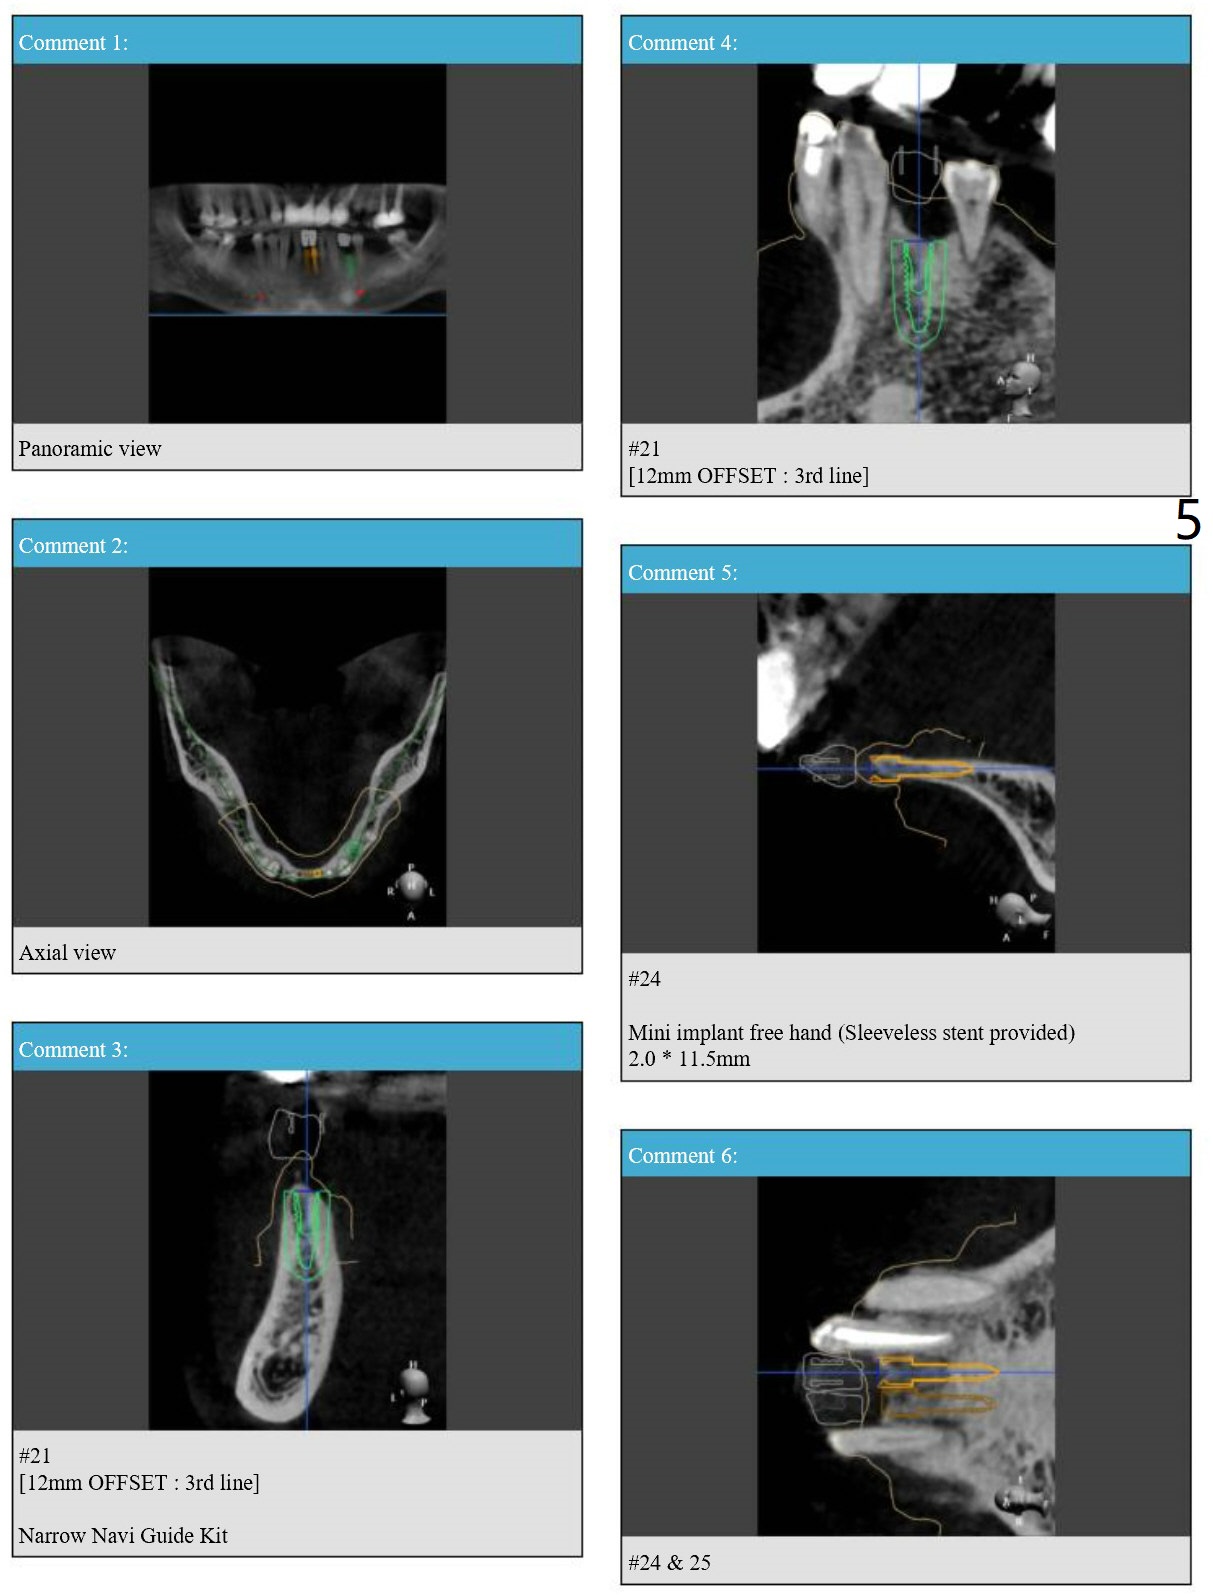

Sleeveless Stent for #24,25 DIO 2 mm 1-piece Implants; IS Guide for #21 IBS Implant

Return to Lower Incisor Premolar Immediate Implant, Trajectory 1-Piece